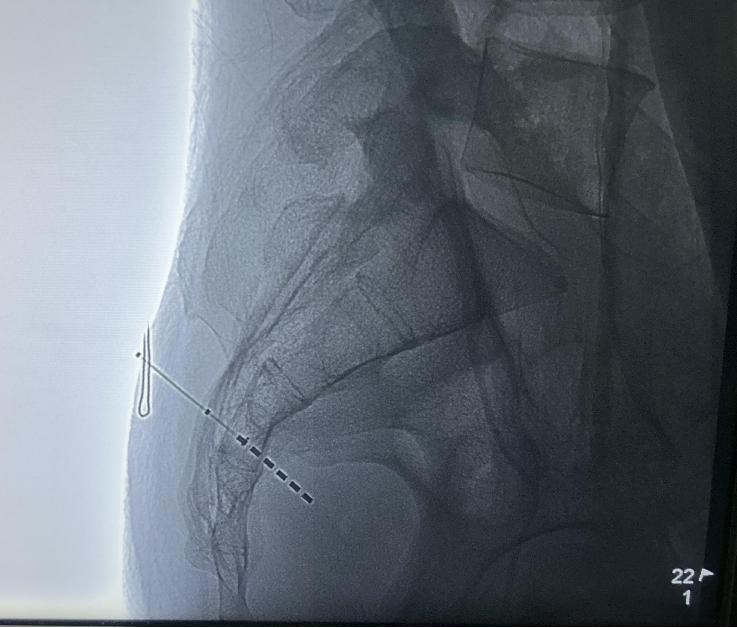

2024年6月19日,方克伟教授、杨童欣博士、杨志忠医师等为患者实施了国产创新六触点骶神经调控一期电极植入术,手术过程顺利,一针穿刺即达目标,术中测试极低的电压即可出现良好的S3神经反应,电机位置佳。

17192775449555.png

术中点位图片